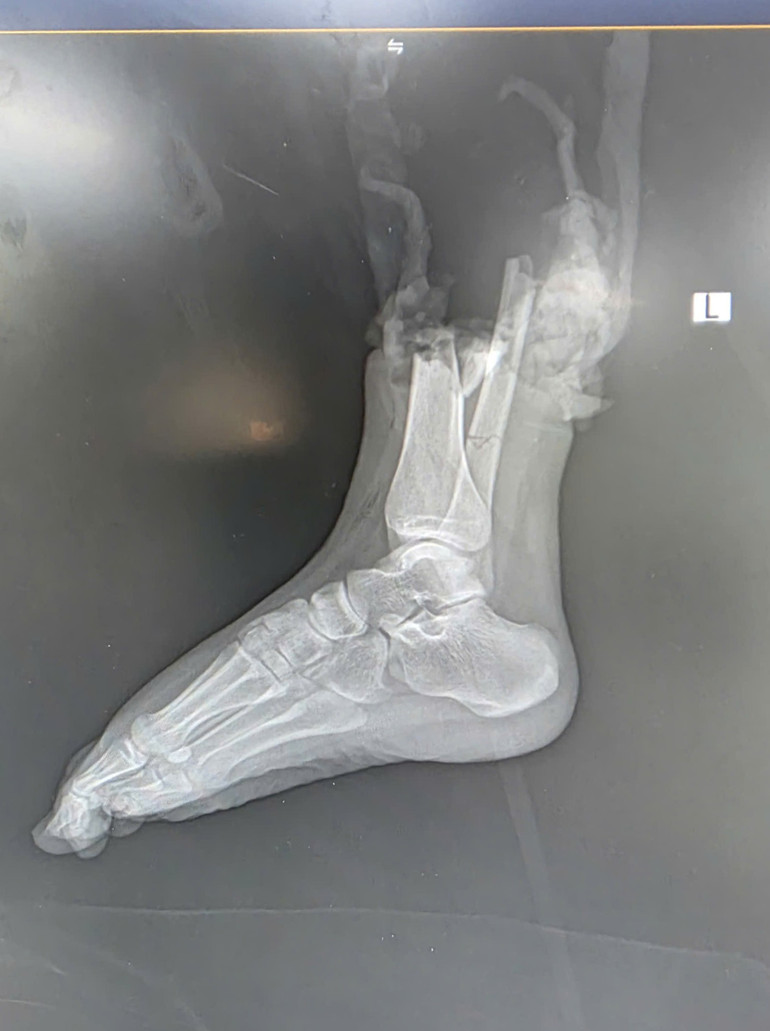

ក្នុងពេលយប់ ក្រុមវេជ្ជសាស្រ្ដបានធ្វើការកម្ទេចចោលយ៉ាងឆាប់រហ័ស ព្យាបាលរបួស និងភ្ជាប់សរសៃឈាម សរសៃប្រសាទ សរសៃពួរ និងឆ្អឹងឡើងវិញ។ ក្រោយពីវះកាត់យ៉ាងខ្លាំងអស់រយៈពេលជាង៦ម៉ោង ដៃជើងដែលដាច់នោះត្រូវបានភ្ជាប់មកវិញដោយជោគជ័យ។ ជិត 2 សប្តាហ៍បន្ទាប់ពីការវះកាត់ អ្នកជំងឺមានសុខភាពល្អ និងអាចផ្លាស់ទីម្រាមជើងរបស់គាត់ ដោយបង្ហាញពីលទ្ធផលវិជ្ជមាននៃការជាសះស្បើយឡើងវិញ។

លោកវេជ្ជបណ្ឌិត Nguyen Dien Thanh Hiep នាយកដ្ឋានវះកាត់អវៈយវៈខាងលើ និងមីក្រូវះកាត់ មានប្រសាសន៍ថា នេះជាករណីដ៏លំបាកមួយ ដោយសារអ្នកជំងឺនៅក្មេង ដៃជើងខូចមានភាពស្មុគស្មាញ ហើយការរក្សាទុក និងដឹកជញ្ជូនមានរយៈពេលយូរ។ ទោះបីជាយ៉ាងណាក៏ដោយ ដោយសារជំនួយដំបូងត្រឹមត្រូវ និងការរក្សាអវយវៈ រួមជាមួយនឹងការសម្របសម្រួលដោយរលូនរវាងក្រុមវះកាត់ ការប្តូរអវយវៈគឺទទួលបានជោគជ័យដ៏អស្ចារ្យ។